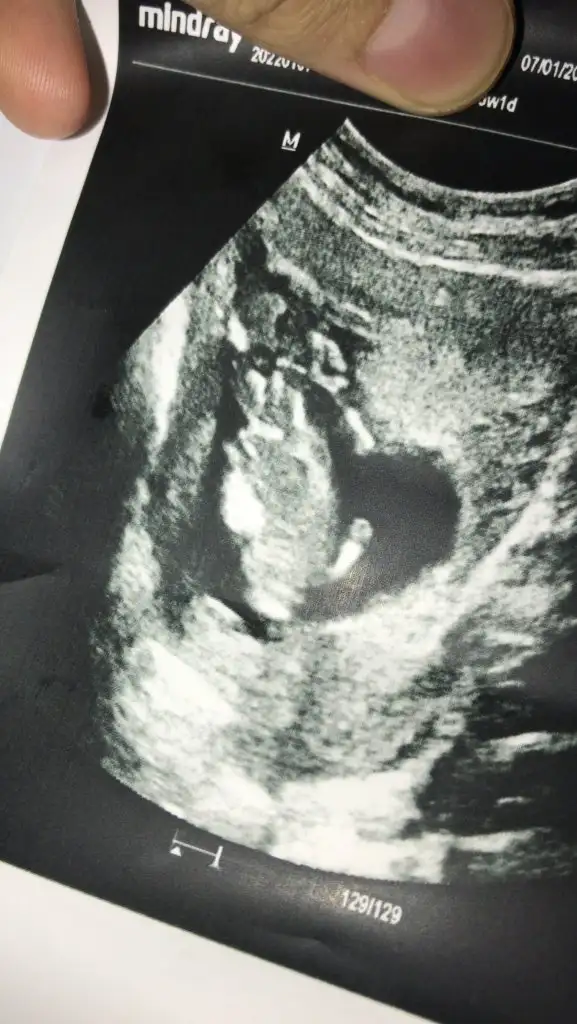

Kiz görünüyorMerhabalar 12+0 haftaligim cinsiyet tahmini yaparmisiniz isminizi temmuz annelerinden duydumIkra meyra

Erkek gibiCinsiyet ne bakabilir misiniz?Ikra meyra

Emin değilim ama sanki erkek gibi başka USG varsa paylaşınMerhaba benimkisi 12 haftalık tam. Bakar mısın lütfen. Doktor 10. Haftada erkeğe benzetti ama bugün de kız gibi dedi :)

Erkek gibi sankiBuna da bakar mısınız 12+6Ikra meyra

Çok teşekkür ederim vakit ayırıp baktığınız için 1 ay sonrasına gün attı doktorum kesinlesir kesinlesmez paylasicamKiz görünüyor